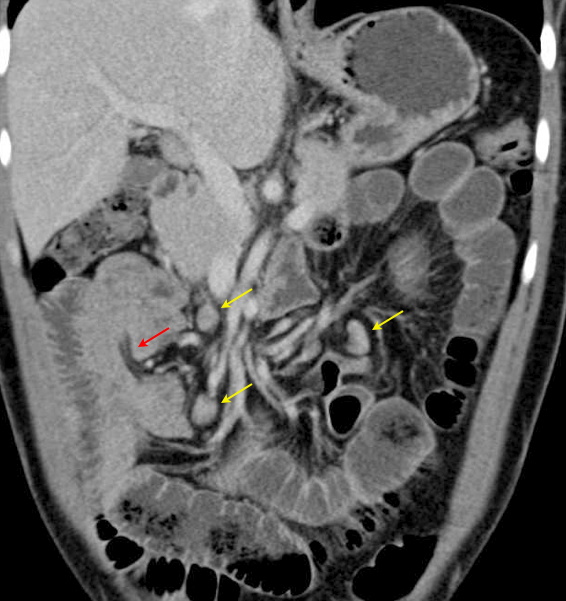

Paciente do sexo masculino, jovem, com história de dor abdominal intensa.

Tomografia, plano axial pós contraste endovenoso. Observamos distensão de alças intestinais com morfologia de delgado (seta vermelha), com níveis líquidos (seta amarela) e inclusões gasosas de permeio.

Tomografia, plano axial. Individualizamos linfonodos mesentéricos com aumento das dimensões (seta amarela). Nota-se também, imagem arredondada com formato similar a um "alvo" (seta vermelha) contendo área central hipoatenuante com densidade de gordura e alguns focos com alta densidade de permeio.

Tomografia, plano coronal. As setas amarelas destacam os linfonodos mesentéricos e a seta vermelha caracteriza melhor a área central hipoatenuante da imagem anterior. Trata-se de uma Intussuscepção intestinal, onde o segmento em questão telescopa o segmento intestinal adjacente determinado semi-obstrução / obstrução intestinal.